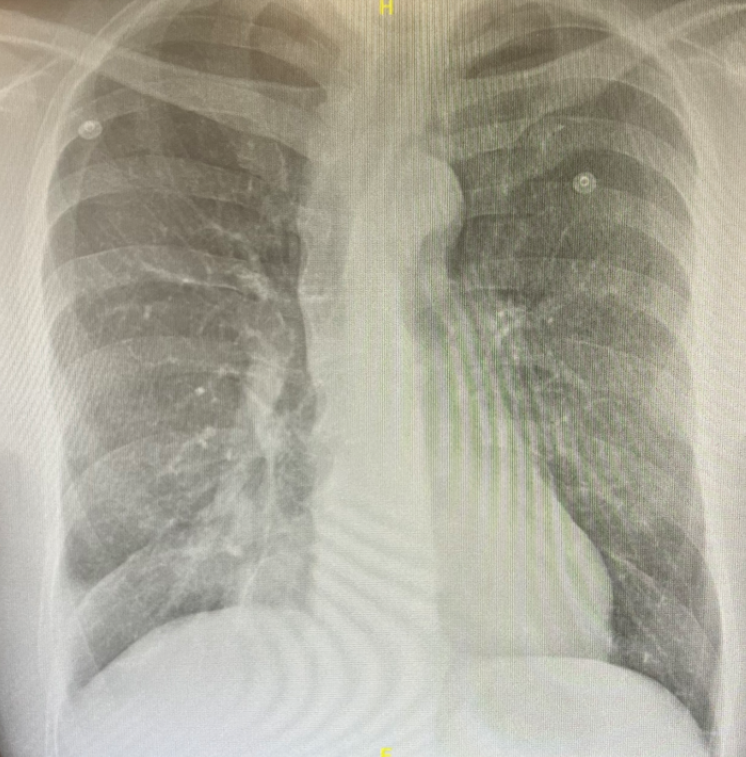

Rx tórax PA: Sin alteraciones pleuropulmonares de interés. Sin cardiomegalia.

Ecografía pulmonar a pie de cama: Líneas A en ambos ápex y campos pulmonares. Imagen de hepatización pulmonar en base derecha.

Neumonía en lóbulo inferior derecho (LID).

En este caso, la ecografía en la urgencia ayudó a objetivar la condensación neumónica en LID que no se conseguía ver en la Rx torax PA previamente realizada, que junto a la alta sospecha clínica de posible infección respiratoria, ayudó a iniciar el tratamiento antibiótico dirigido y evitar pruebas complementarias innecesarias.